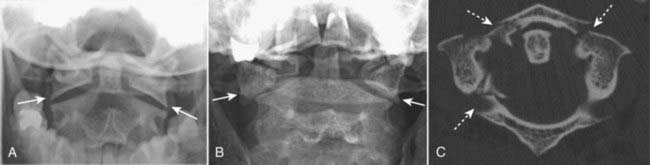

image A Jefferson’s fracture is a fracture of C1 usually involving both the anterior and posterior arches. In its classical presentation, there are bilateral fractures of both the anterior and posterior arches of C1 producing four fractures in all.

image It is caused by an axial loading injury (such as diving into a swimming pool and hitting one’s head on the bottom).

imageOn conventional radiographs, the hallmark of a Jefferson fracture is bilateral, lateral offset of the lateral masses of C1 relative to C2 as seen on the open-mouth view (atlantoaxial view) of the cervical spine. The fracture is confirmed utilizing CT (Fig. 24-18).

image A Jefferson’s fracture is a “self-decompressing” fracture in that the spinal canal at the level of the fracture is wide enough to accommodate any swelling of the cord. There is usually no neurologic deficit associated with this type of fracture.

image

Figure 24-18 Normal open-mouth view, Jefferson’s fracture open-mouth view, and CT.

A Jefferson’s fracture is a fracture of C1 usually involving both the anterior and posterior arches. A, The normal “open-mouth” view of C1 and C2 demonstrates that the lateral margins of C1 (solid white arrows) line up with the lateral margins of C2. B, The hallmark of a Jefferson’s fracture is bilateral, lateral offset of the lateral masses of C1 (solid white arrows) relative to C2. C, The fracture is confirmed utilizing CT, which shows fractures of both the right and left anterior arch and the right posterior arch of C1 (dotted white arrows).